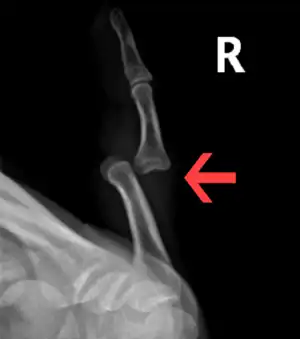

X ray of a dislocated PIP joint (dorsal) of the 5th finger

Common causes include sports that involve balls and gymnastics.[3] The underlying mechanism generally involves the finger getting bent backwards.[5] They includes DIP dislocations, PIP dislocations (most common), and MCP dislocation.[2][5] The most commonly affected MCP joint is that of the thumb.[4] Diagnosis is by X-rays.[1] They can be classified as dorsal, volar, or lateral based on the position of the bone farthest from the body.[2]